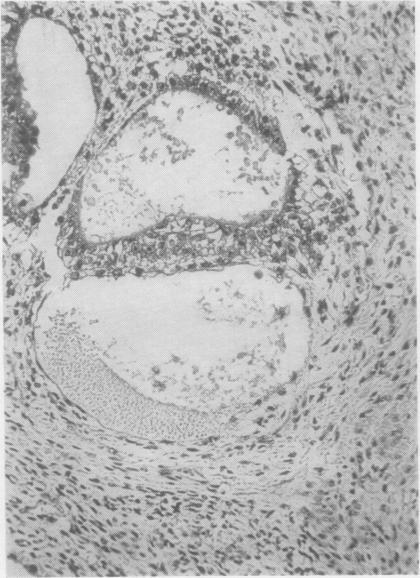

Developmental stages of embryo-like bodies in teratoma testis.